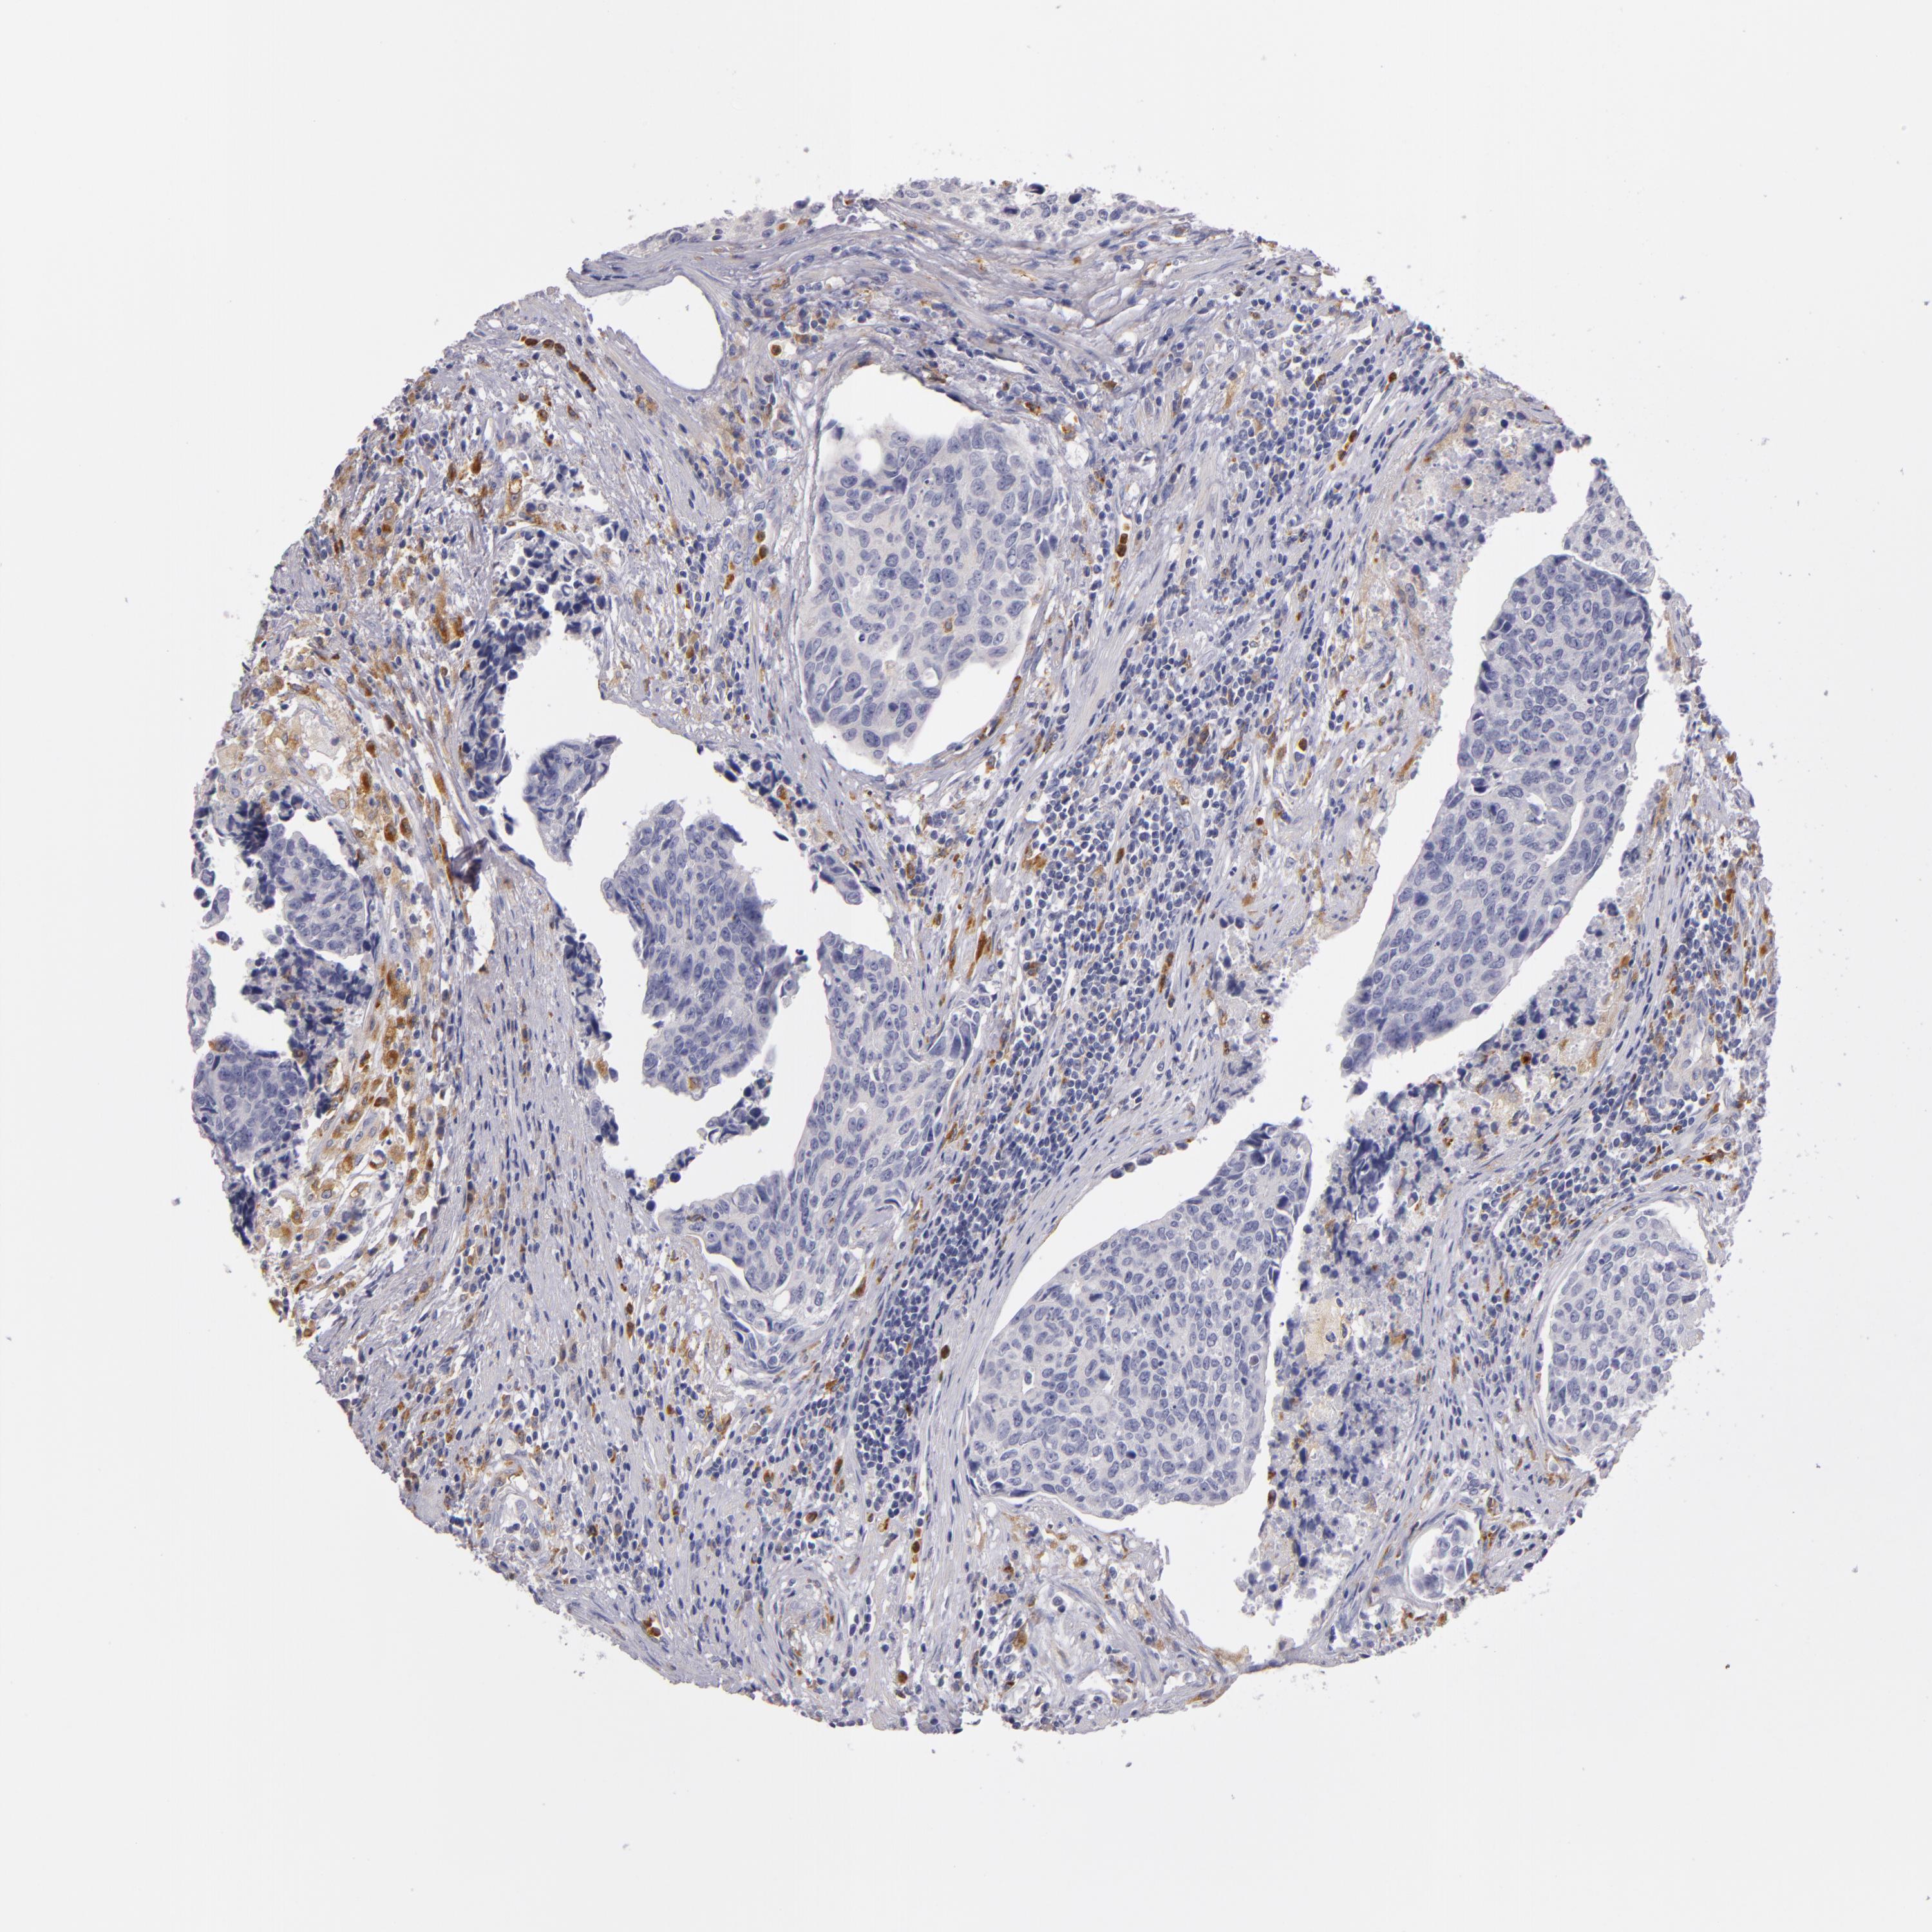

UROTHELIAL CANCER - Protein expressioni

A mouse-over function shows sample information and annotation data. Click on an image to view it in a full screen mode. Samples can be filtered based on level of antibody staining by selecting one or several of the following categories: high, medium, low and not detected. The assay and annotation is described here.

Note that samples used for immunohistochemistry by the Human Protein Atlas do not correspond to samples in the TCGA dataset.

Antibody stainingi

Antibody staining in the annotated cell types in the current human tissue is reported as not detected, low, medium, or high, based on conventional immunohistochemistry profiling in selected tissues. This score is based on the combination of the staining intensity and fraction of stained cells.

Each image is clickable and will lead to virtual microscopy that enables deeper exploration of all samples and also displays staining intensity scores, fraction scores and subcellular localization as well as patient and tissue information for each sample.

Antibody HPA001608

Staining

High

Medium

Low

Not detected

Intensity

Strong

Moderate

Weak

Negative

Quantity

>75%

75%-25%

<25%

None

Location

Nuclear

Cytoplasmic/membranous

Cytoplasmic/membranous,nuclear

Urothelial carcinoma, High grade